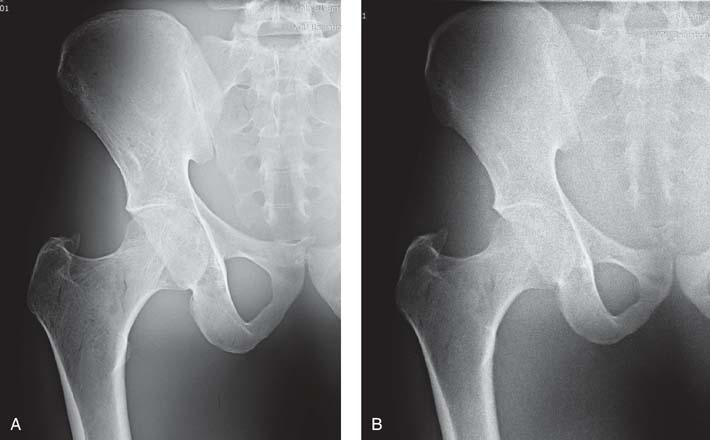

FIG. 6-3 A, Radiographic image obtained with high mAs showing decreased quantum noise. B, Radiographic image obtained with low mAs showing increased quantum noise. (From Johnston JN, Fauber TL: Essentials of Radiographic Physics and Imaging, ed 3, St. Louis, 2020, Elsevier.)

FIG. 6-4 Exposure errors can be computer adjusted to maintain image brightness. A, Image created with sufficient mAs. B, Image created with insufficient mAs, resulting in increased quantum noise visible. C, Image created with excessive mAs, resulting in decreased quantum noise visible. The exposure indicator value reflected the exposure errors to the IR for images B and C. (From Johnston JN, Fauber TL: Essentials of Radiographic Physics and Imaging, ed 3, St. Louis, 2020, Mosby.)

A diagnostic-quality image (Fig. 6-7A) was produced using 70 kVp at 2 mAs. Fig. 6-7B was produced using 50 kVp at 2 mAs, and Fig. 6-7C was produced using 93 kVp at 2 mAs. Although the brightness was adjusted by the computer, the exposure indicator for each of the images varied greatly and reflected the exposure to the IR. When a kVp that is too low is selected, the brightness is adjusted, but quantum noise may be visible. Additionally, when a kVp that is too high is selected without an appropriate decrease in mAs, the image brightness is adjusted, but patient exposure may be increased because of increased x-ray quantity and scatter within the tissues. Although brightness can be computer adjusted when using a kVp that is too high, increased scatter radiation can also reach the IR and may adversely affect image quality.

FIG. 6-7 A, Image produced using 70 kVp at 2 mAs. B, Image produced using 50 kVp t 2 mAs, resulting in higher subject contrast and computer adjusted to maintain brightness but increased quantum noise visible. C, Image produced using 93 kVp at 2 mAs, resulting in lower subject contrast and computer adjusted to maintain brightness, but patient exposure is increased. (From Johnston JN, Fauber TL: Essentials of Radiographic Physics and Imaging, ed 3, St. Louis, 2020, Mosby.)

It is important to note that brightness can be computer adjusted when the mAs is not properly adjusted for adding or changing a grid (Fig. 6-18). However, without proper mAs adjustment when adding or changing a grid, increased quantum noise or unnecessary patient radiation exposure could be the result.

FIG. 6-18 A, A quality image created without a grid. B, An image created with a grid but no adjustment in mAs. This image has higher contrast but increased quantum noise visible. C, Image created with a grid and appropriate mAs adjustment. This image has higher contrast than image A and less quantum noise visible than image B. (From Johnston JN, Fauber TL: Essentials of Radiographic Physics and Imaging, ed 3, St. Louis, 2020, Elsevier.)